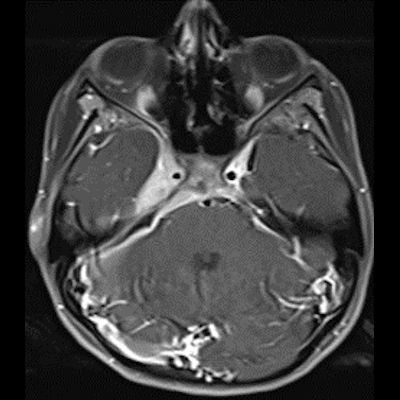

14 yaş, K

Baş ağrısı ve sağda abdusens felci

Sarkoidoz

Nörosarkoidoz

Sağ kavernoz sinüste kontrastlanan ICA yı çevreleyen daraltan yumuşak doku değerleri mevcuttur.Sağ parahiler bölgede lenfadenopati veya kitle lezyonu ile uyumlu olabilecek görünüm mevcuttur.Ayırıcı tanıda Nazofarink Ca metastazı,lenfoma,sarkaidoz,wegener granulomatozu düşünüle bilir.Çocuk hasta olduğu için daha çok lenfoma olarak düşündüm